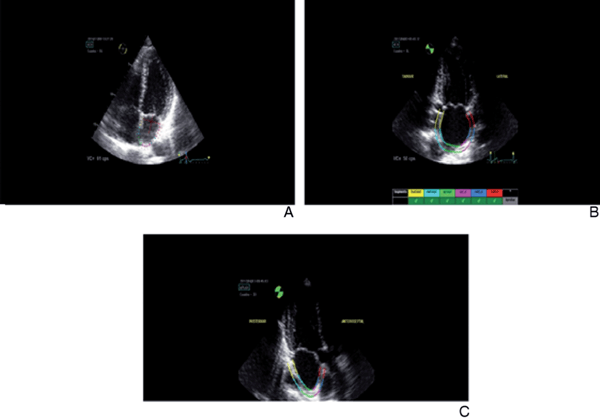

Se estableció el ancho de muestreo (ancho de ROI) como el mínimo ofrecido por el software, dada la poca variación del espesor de la pared auricular durante el ciclo cardíaco y durante los estados patológicos. Luego, el mismo software divide a la pared auricular en seis segmentos equidistantes para cada vista apical (Figura 3).

Figura 3: A) Trazado en vista de 4 cámaras, nótese la no inclusión del anillo mitral dentro de la región de interés. El ancho de la región de interés siempre será el mínimo propuesto por el software. B) Trazado en vista de 2 cámaras, donde el software divide a la aurícula izquierda en seis segmentos equidistantes. Nótese en los segmentos anulares (rojo y amarillo) la pequeña curvatura hacia la luz auricular de la región de interés para mejorar la calidad de seguimiento por el software. C) Trazado de la región de interés en vista de 3 cámaras, nótese la no inclusión de la pared inferior de la aorta dentro de dicha región.